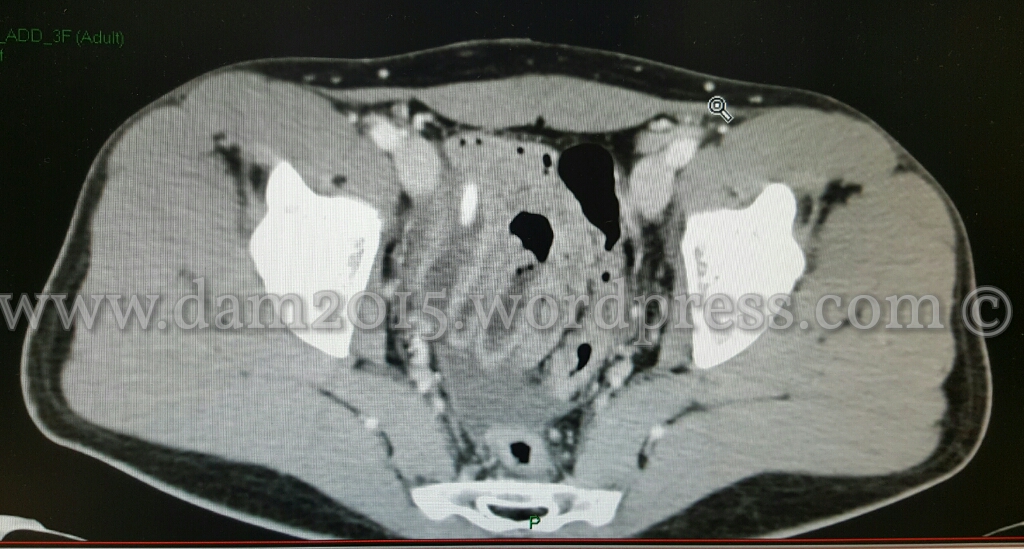

Alla TC con mezzo di contrasto si evidenziava distensione fluida dell’appendice cecale a localizzazione pelvica, nel cui lume si apprezza appendicolita.